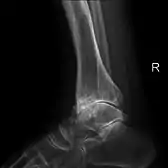

Lateral

Frontal

Secondary osteoarthritis of the ankle (due to an old bone fracture) in an 82-year-old woman